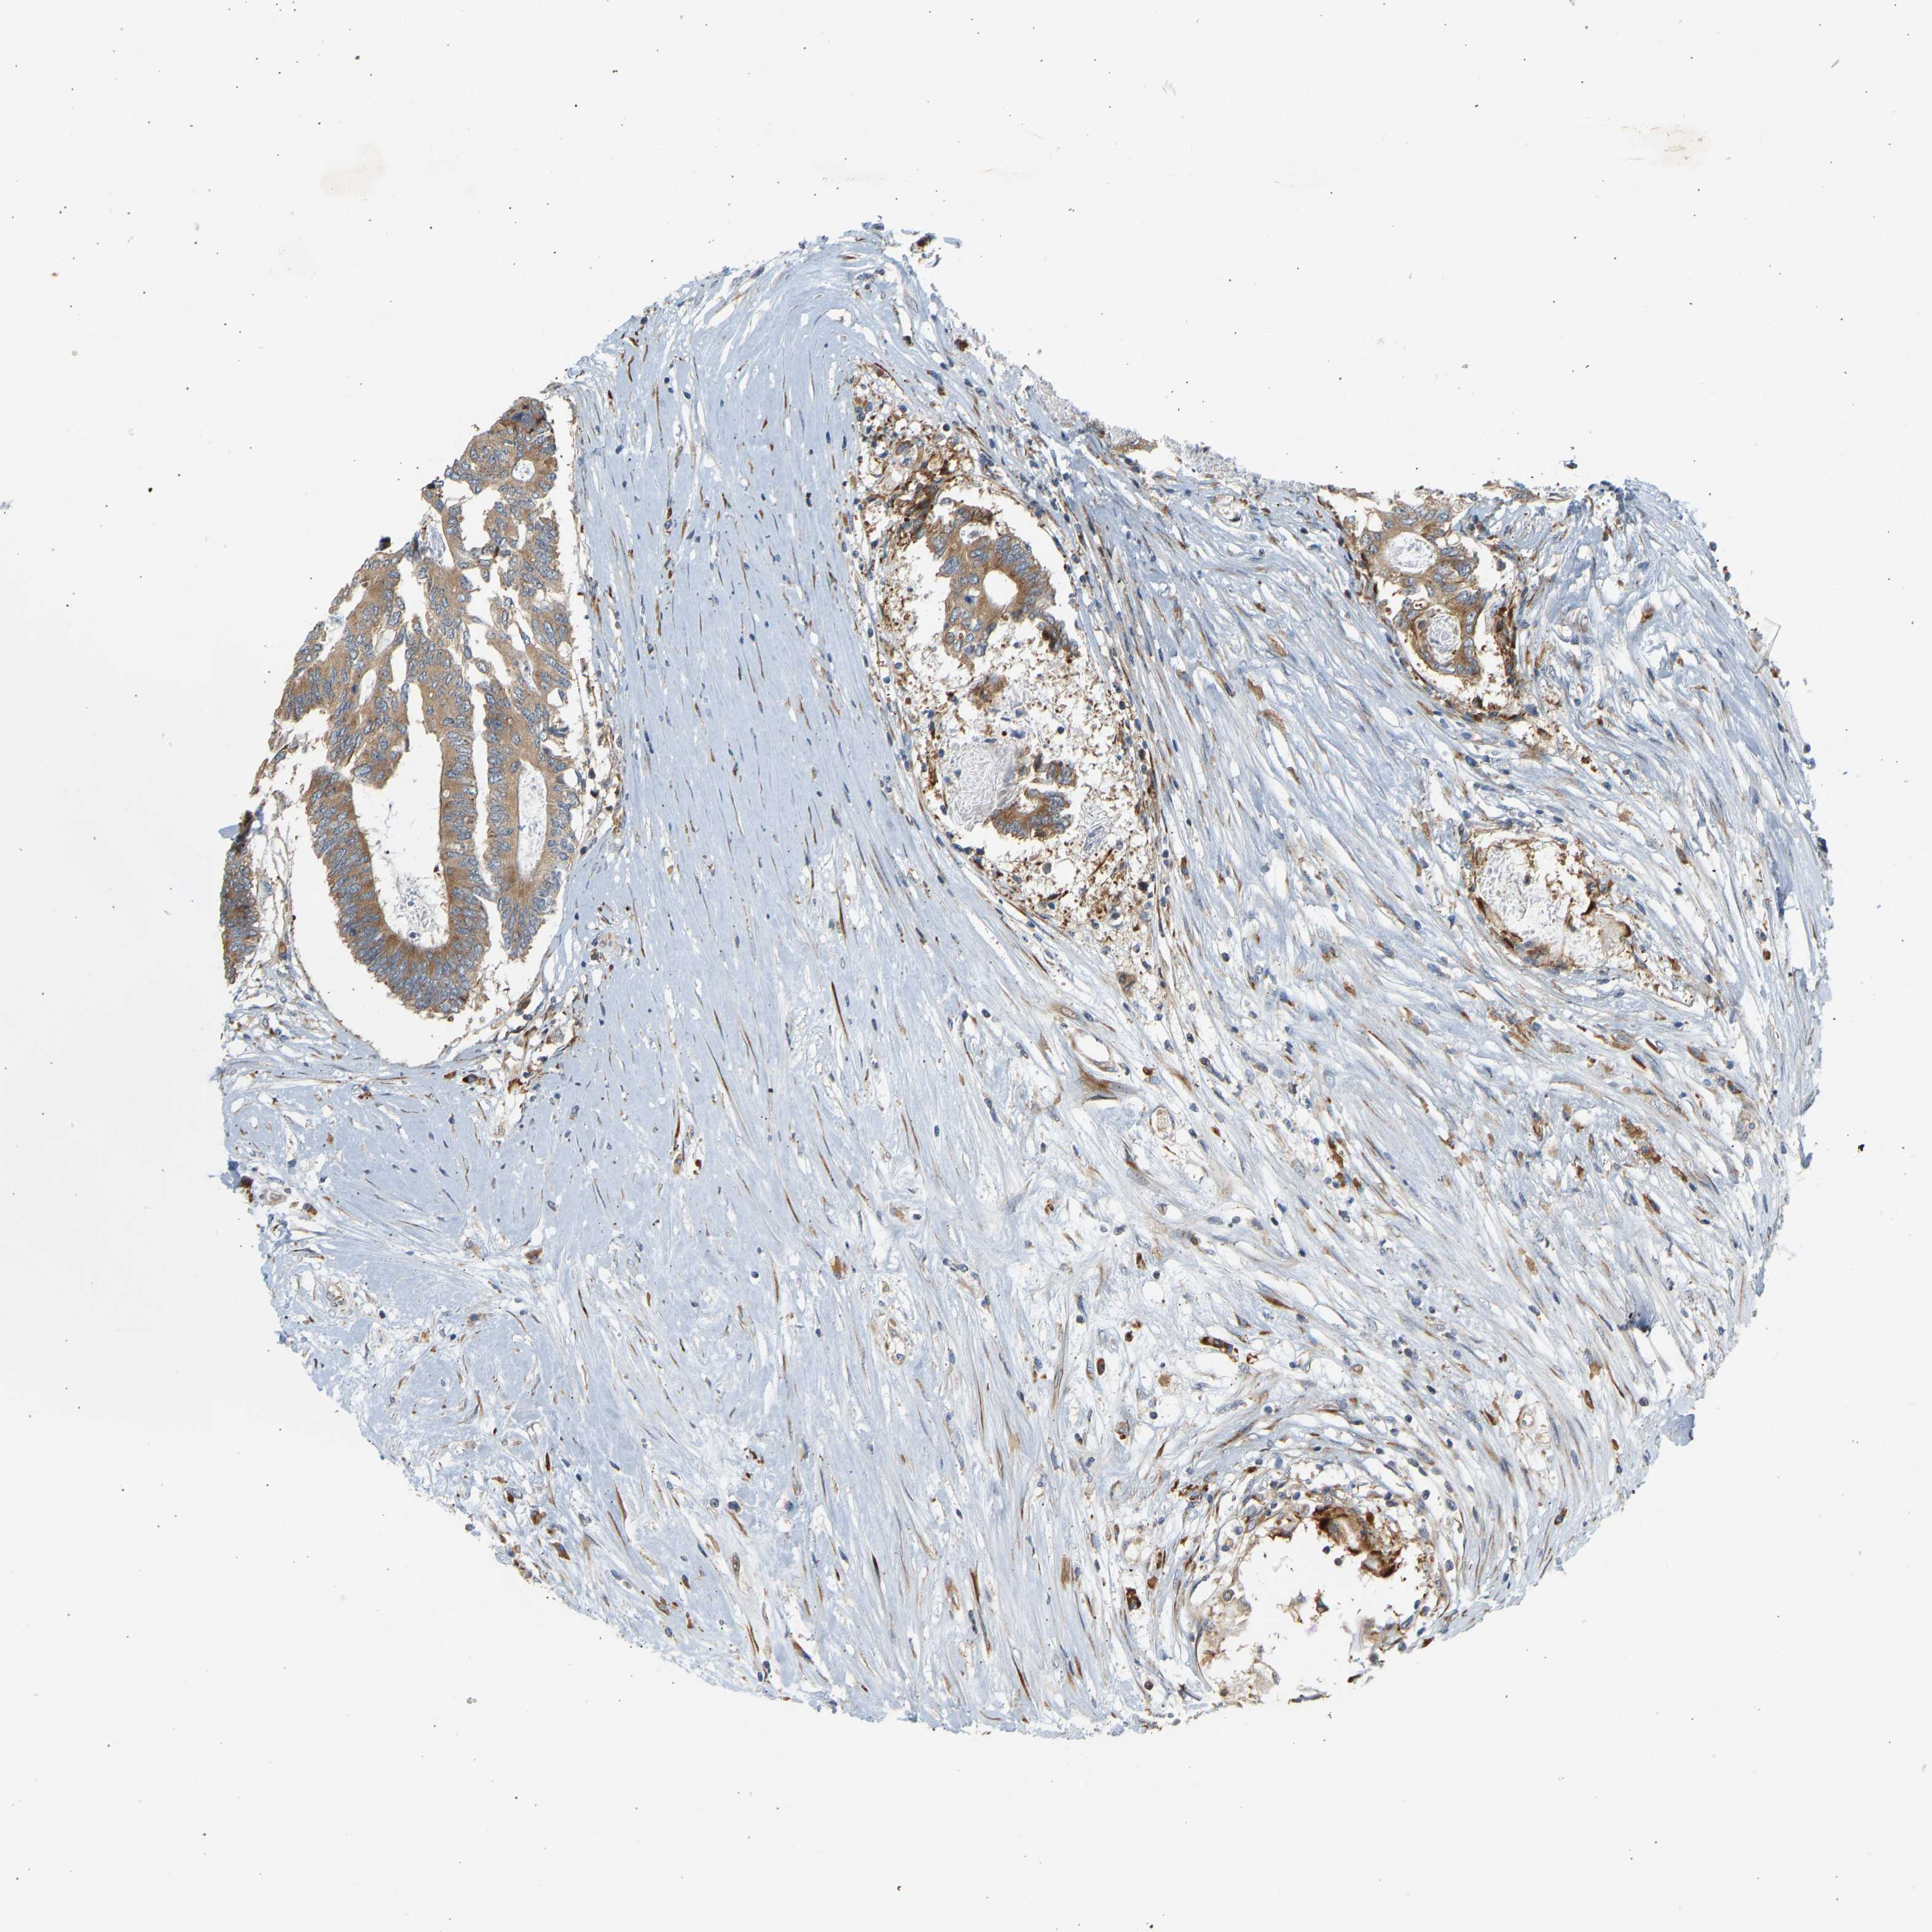

CANCER COLORECTAL CANCER Show tissue menu

ANTIBODIES

AND

VALIDATION